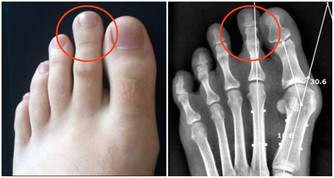

專家建議服用鈣片前後2小時內,不要進食菠菜。 4、鈣片+菠菜 菠菜中含有大量草酸鉀,進入人體後電解出的草酸根離子會沉澱鈣離子,不僅妨礙人體吸收鈣,還容易生成草酸鈣結石。專家建議服用鈣片前後2小時內,不要進食菠菜,或先將菠菜煮一下,待草酸鉀溶解於水,將水倒掉後再食用。 5、降壓藥+葡萄柚汁 服用降壓藥期間不能飲用葡萄柚汁。因為葡萄柚汁中的柚皮素成分會影響肝臟中某種酶的功能,而這種酶與降壓藥的代謝有關,將造成血液中藥物濃度過高,副作用大大增加。